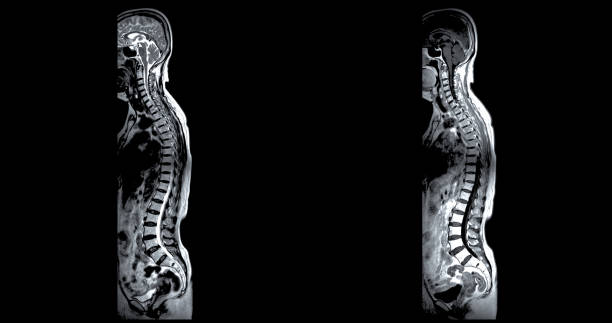

허리디스크는 많은 사람들에게 고통을 주는 흔한 건강 문제 중 하나입니다.

허리디스크를 치료하고 예방하기 위해서는 올바른 자세와 방법이 필요합니다.

이 글에서는 허리디스크를 낫게 하는 데 도움이 되는 요추 전만 자세를 정리합니다.

요추 전만 자세의 중요성

요추 전만은 허리디스크 치료와 예방에서 핵심적인 역할을 합니다. 요추 전만을 만들면 디스크의 압력이 감소하고 허리디스크 증상을 완화할 수 있습니다. 이를 위한 두 가지 자세가 있습니다.